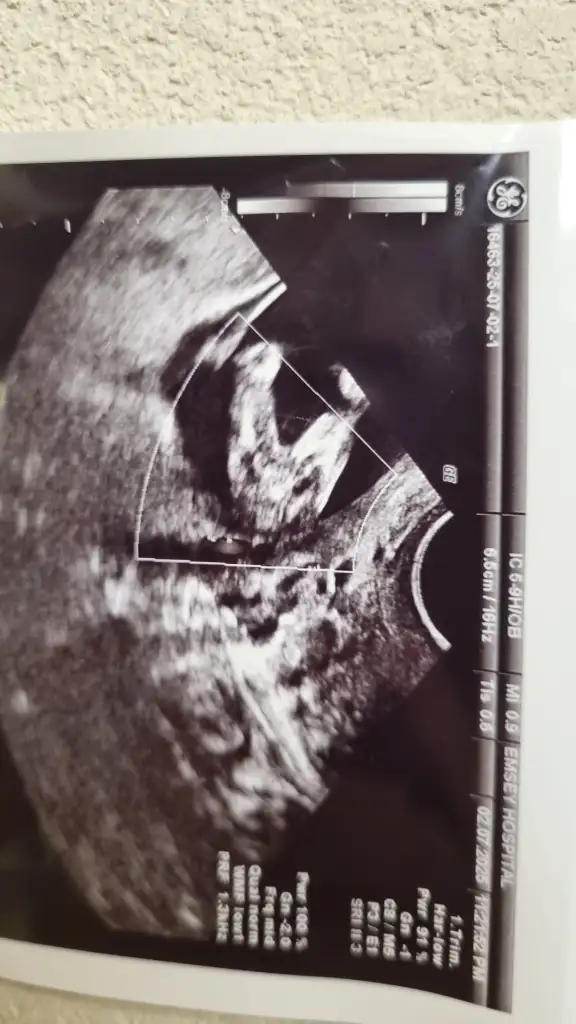

Benimkinde belli mi acabaUltroson fotoğrafından pek belli olmuyor sizin genelde nub teorisi doğru çıkıyor nub gözükmüyor sizinkinde

Bacaklarını toplamış o yüzden pek gözükmüyor 10 haftalık bir görüntüsü var vajinal daha net gibi atayım bakınUltroson fotoğrafından pek belli olmuyor sizin genelde nub teorisi doğru çıkıyor nub gözükmüyor sizinkinde

Sizinkinde başı bile göremedim benBenimkinde belli mi acaba